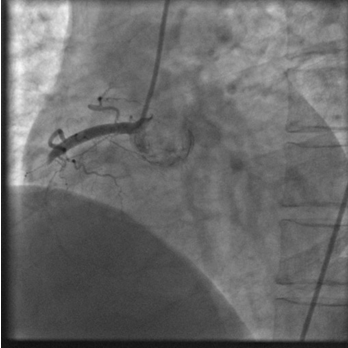

右冠脉完全堵塞造成急性下壁心肌梗死